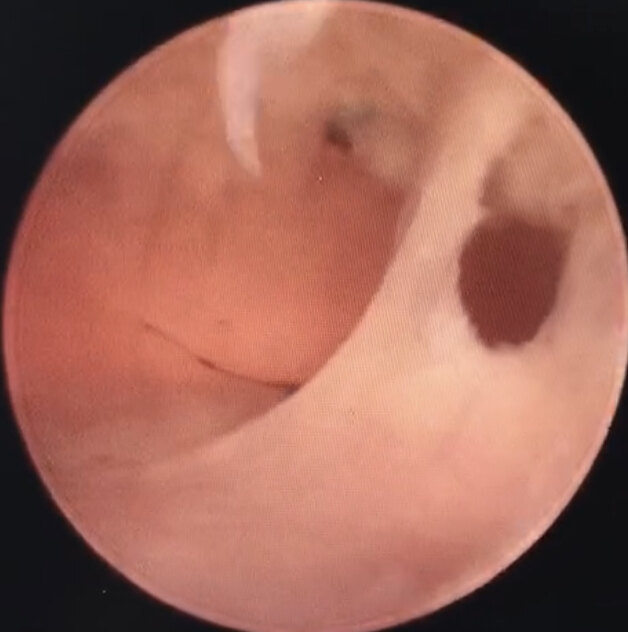

聊一聊內(nèi)膜疤痕的話題

應(yīng)讀者要求,2021年的開篇,我們聊一下內(nèi)膜疤痕的話題。在全國各地如火如荼開展宮腔鏡電能量器械手術(shù)的背景下,這個(gè)話題有點(diǎn)不切時(shí)宜,反其道而行之,所以一直在猶豫要不要寫。但隨著全國各地越來越多的內(nèi)膜疤痕的患者,感到自己有責(zé)任把臨床的經(jīng)驗(yàn)和體會分享給大家,減少疤痕的發(fā)生,挽救子宮,保護(hù)生育功能。 在我征集這個(gè)話題的材料時(shí),是我的患者給予我最大的熱情和支持。所以該文圖片和案例均出自我的患者,在此表示感謝。 什么是內(nèi)膜疤痕?在了解這個(gè)話題之前,我們先來說說宮腔粘連。 宮腔粘連是以色列Asherman教授于1948年描述的,由于子宮內(nèi)膜基底層損傷后修復(fù)障礙導(dǎo)致的宮腔部分或全部閉塞,從而引起的月經(jīng)異常、周期性腹痛、不孕和反復(fù)流產(chǎn)等一系列并發(fā)癥。 宮腔粘連從性質(zhì)上來分,可分為三種: 1、膜性粘連 從粘連性質(zhì)上來說,這是最輕的一種粘連,可以鈍性、銳性分離,是預(yù)后最好的一種粘連方式。 2、纖維性粘連 有纖維結(jié)締組織增生,組織比較疏松,易于分離。 3、肌性粘連 豐富致密的纖維結(jié)締組織增生,質(zhì)地偏硬,創(chuàng)面大。 目前中國宮腔粘連共識從性質(zhì)上是分為以上三種。 個(gè)人認(rèn)為:內(nèi)膜的疤痕粘連或疤痕化改變,是最嚴(yán)重的宮腔粘連的表現(xiàn)形式。雖然從性質(zhì)上來講,疤痕也是纖維結(jié)締組織的增生導(dǎo)致,但其質(zhì)地硬,組織損傷程度加重,可以造成宮腔的疤痕攣縮,破壞力更大,愈后不容樂觀,甚至醫(yī)生無從下手,最后放棄。所以在這里估且認(rèn)為它是第四種粘連的形式。 4、內(nèi)膜疤痕 從照片上可以看到,疤痕組織質(zhì)地致密、厚重,組織蒼白,由此可以想象手術(shù)難度。那么為什么造成疤痕?疤痕是否能夠手術(shù)?手術(shù)后是否能夠恢復(fù)?恢復(fù)的程度又如何?是否還能夠正常生育? 這是大家共同關(guān)心的話題。 為什么會形成疤痕?我們知道宮腔的手術(shù)操作,比如人流、清宮等會造成內(nèi)膜基底層的損傷。 對基底層損傷的程度決定宮腔粘連的性質(zhì)和程度。損傷的越重,粘連的性質(zhì)越重,手術(shù)難度加大,恢復(fù)就會越差。 疤痕做為最嚴(yán)重的粘連形式,內(nèi)膜基底層的損傷也是最重的。除了內(nèi)膜結(jié)核的感染造成,多次宮腔手術(shù)操作,尤其是現(xiàn)在廣泛開展的宮腔電外科手術(shù)操作,更是比較常見。所以問患者病史有宮腔鏡手術(shù)操作的,一定會再追問一下,有沒有電切?! 通過上述案例提示我們,多次宮腔操作,對宮腔內(nèi)膜損傷會加重。也警示我們,盡量減少宮腔多次手術(shù),選擇有經(jīng)驗(yàn)的醫(yī)生,以最少最有效的手術(shù)來達(dá)到治療的目的。 如果大家對宮腔、內(nèi)膜沒有概念,下面可以看看正常的宮腔和內(nèi)膜 正常的宮腔內(nèi)膜,我們比喻為土壤,它為胚胎提供一個(gè)溫暖、松軟、營養(yǎng)豐富的環(huán)境,有利于胚胎的種植、生長和發(fā)育。子宮腔也隨胚胎發(fā)育而相應(yīng)的擴(kuò)大,為胚胎提供一個(gè)舒適的有包容性的房子。這需要子宮的組織結(jié)構(gòu)是有彈性,有伸展性。 反觀疤痕的內(nèi)膜,正常的組織結(jié)構(gòu)消失,功能消失,彈性消失,質(zhì)地僵硬,顏色蒼白,血供差,這樣的宮腔,胚胎怎么能夠著床?即使著床,又怎么能夠發(fā)育?這樣的內(nèi)膜,就是我們俗稱的水泥地,水泥地上怎么能夠開花結(jié)果呢? 為什么電切更容易導(dǎo)致內(nèi)膜疤痕?首先我們要了解內(nèi)膜的結(jié)構(gòu) 子宮內(nèi)膜分為功能層和基底層兩部分,隨著卵泡發(fā)育及排卵,以雌激素為主過度到以孕激素為主,子宮內(nèi)膜呈現(xiàn)由增殖期至分泌期的改變。至黃體萎縮,孕激素撤退,內(nèi)膜螺旋血管出現(xiàn)痙攣性收縮,導(dǎo)致內(nèi)膜組織缺血壞死、剝脫,脫落,內(nèi)膜碎片隨血液一起流出,即月經(jīng)來潮。 隨著卵巢周期的恢復(fù),內(nèi)膜的周期性也周而復(fù)始,即內(nèi)膜功能層周期性脫落,其下基底層周期性生長內(nèi)膜。故普通的觀點(diǎn)認(rèn)為基底層是有內(nèi)膜干細(xì)胞的,以滿足內(nèi)膜周期性生長的需要。所以基底層內(nèi)膜再生功能決定內(nèi)膜的特性。 宮腔粘連的發(fā)生發(fā)展,就是損傷基底層付出的代價(jià)。損傷的越重,再生功能就會越差。 宮腔粘連的形成機(jī)制上除了基底層損傷,造成纖維結(jié)締組織過度增生外,還有一個(gè)宮頸神經(jīng)反射學(xué)說:宮頸內(nèi)口是一特殊的神經(jīng)分布區(qū)域,多次進(jìn)出宮腔的手術(shù)操作,可造成反射性神經(jīng)痙攣并呈持續(xù)性痙攣狀態(tài),可能會造成供血障礙及對卵巢激素不敏感。 懂得了基本的原理,那么電切對子宮內(nèi)膜的破壞就相對容易理解。 宮腔粘連的手術(shù)操作的方式有兩種。 一種是冷刀,即微型剪刀 冷刀也有單開剪、雙開剪、硬剪、軟剪之分,每個(gè)醫(yī)生的習(xí)慣不同而選擇不同。 冷刀的優(yōu)點(diǎn)在于: 1、機(jī)械能:利用剪刀手的持剪開合來修復(fù)宮腔,沒有電能輔射。有經(jīng)驗(yàn)的醫(yī)生一般不會造成額外的損傷。 2、因?yàn)闆]有額外的電輔射損傷,相應(yīng)的保護(hù)了殘留基底層的內(nèi)膜再生功能,尤其適用于有生肓要求的女性。 3、可適用于粘連、息肉等手術(shù),目前的HEOS冷刀系統(tǒng)還可用于0-2型的子宮肌瘤手術(shù)。 4、適用于mini宮腔鏡,無需擴(kuò)宮,保護(hù)宮頸機(jī)能。 冷刀的缺點(diǎn): 1、費(fèi)時(shí)費(fèi)力費(fèi)錢 因?yàn)槿淌侨斯げ僮?,而且疤痕組織質(zhì)地硬,所以費(fèi)時(shí)費(fèi)力,我們的剪刀手常常手上磨皮、起泡、磨老繭。 微型剪刀屬于精細(xì)手術(shù)器械,因?yàn)橘M(fèi)時(shí)費(fèi)力,所以很容易耗損,屬于易耗品,需要不斷添新,所以費(fèi)錢。醫(yī)院要核算成本,成本提高。 有人會說,有的粘連微型剪刀是沒有辦法的。這是不了解粘連組織的特性。任何粘連,剪刀都可以修剪,前提是不要用已磨損、鈍的剪刀。 磨刀不誤砍柴工。 工欲善其事 ,必先利其器。 2、術(shù)中出血 影響術(shù)野 因?yàn)榧舻对谛藜艚M織的過程中容易出血,造成視野不清晰。也因?yàn)榧舻稕]有電凝止血功能,會比電切手術(shù)出血多一點(diǎn),臨床上會用縮宮素,子宮肌肉收縮,夾閉血管來止血。 而另一種手術(shù)方式,就是廣泛采用的電刀。它分為針狀電極、環(huán)狀電極。 大家看到圖片,每一次電刀的運(yùn)行,都會放射電火花,利用電能的高溫來切割或切除組織,這就對組織產(chǎn)生了電輔射損傷。 這張是電切術(shù)畢的照片,部分組織已炭化,術(shù)后內(nèi)膜的恢復(fù)不容樂觀。 全國有不少宮腔鏡手術(shù)的專家,他們經(jīng)驗(yàn)豐富,手術(shù)嫻熟,運(yùn)刀快速如行云流水,相應(yīng)減少了電刀與組織接觸的時(shí)間,也減輕了對組織的電輔射損傷。也有專家在電刀處理時(shí),減少切割次數(shù),以減輕電損傷。但有時(shí)即使這樣,也避免不了疤痕的產(chǎn)生,復(fù)粘的發(fā)生。臨床上可以看見一些病例:一次電切后,后面次次宮腔鏡,次次復(fù)粘。因?yàn)檫@種手術(shù)方式的本質(zhì)不能排除電輔射損傷,形成疤痕,疤痕處理不好,就會反復(fù)粘連,反復(fù)宮腔鏡。我做得最多的一例已經(jīng)術(shù)前做過22次宮腔鏡了。 所以現(xiàn)在有專家呼吁,對有生育要求的宮腔粘連手術(shù)盡可能用冷刀處理,避免電損傷。 目前上海的生殖中心的宮腔粘連手術(shù)均是采用冷刀。保護(hù)卵巢功能,這個(gè)觀點(diǎn)已經(jīng)深入人心。我們在腹腔鏡卵巢手術(shù)中,在達(dá)到手術(shù)目的的前提下,盡可能避免使用電能或減少電能對卵巢作用的時(shí)間,并且用生理鹽水在電能作用的創(chuàng)面給予降溫。 同理,電能也會對子宮內(nèi)膜基底層產(chǎn)生破壞,破壞力與原有組織損傷的程度、手術(shù)經(jīng)驗(yàn)、技巧、時(shí)間、部位等等相關(guān)。電輔射不僅僅體現(xiàn)在切割的創(chuàng)面,可能對創(chuàng)面周圍及其下方的組織都有電的輔射損傷作用,相應(yīng)損傷作用面積加大,這是個(gè)潛在的損傷。高溫對基底層內(nèi)膜干細(xì)胞的作用是否會與電能對卵巢皮質(zhì)的破壞程度相似,目前還沒有這方面的研究。 全國各地都在開展宮腔粘連電切手術(shù),肯定這種手術(shù)方式治愈了很多的患者。但愿上面圖片只是滄海一粟。 我們也來說說電切的優(yōu)點(diǎn)吧。 1、手術(shù)快,時(shí)間短 因?yàn)殡姷哆\(yùn)行快,術(shù)中出血少,視野暴露清楚,相應(yīng)手術(shù)時(shí)間縮短。 2、出血少,術(shù)中視野清晰 因?yàn)殡姷侗旧砭陀须娔沟淖饔?,所以術(shù)中出血少,幾乎無血狀態(tài),相應(yīng)術(shù)野清晰。 3、器械耗損率低 電刀的先期投入比單純的剪刀要多,但后期相應(yīng)耗損沒有精細(xì)的微型剪刀頻繁,相應(yīng)性價(jià)比高。 4、可以處理肌瘤類手術(shù) 在HEOS和刨削系統(tǒng)問世前,電刀是處理較大肌瘤的唯一法寶,因?yàn)槲⑿图舻秾^大肌瘤而言是不太現(xiàn)實(shí)的。 5、節(jié)省人力 除了巡回等協(xié)助,手術(shù)臺上一名主刀醫(yī)生即可完成。而微型剪刀,有時(shí)需要剪刀手來做助手。 電刀的缺點(diǎn): 1、電輔射損傷:上面已講述。 2、需要擴(kuò)宮: 電刀目前絕大多數(shù)都需要擴(kuò)宮至10號,潛在的就有可能破壞宮頸的微結(jié)構(gòu),造成宮頸松馳。臨床上見過不少電切后的宮頸比較松馳,再次手術(shù)置放防粘連支架容易下移或脫落。是否還會引起宮頸機(jī)能不全,有待研究。國外有文獻(xiàn)報(bào)道,數(shù)據(jù)顯示是有影響的。 內(nèi)膜疤痕的治療內(nèi)膜疤痕能否治療,很多醫(yī)生都持懷疑態(tài)度的。就如同我們的皮膚,損傷或者燒傷形成瘢痕以后,除了植皮,否則不可能長出新生的皮膚組織。 但內(nèi)膜是會隨著月經(jīng)脫落,周期性再生的,是否手術(shù)后能有所改善或恢復(fù)呢? 我前面文章里有一個(gè)病例,這可能是促使我開始去關(guān)注內(nèi)膜疤痕。 這個(gè)病人因?yàn)?次宮腔鏡沒有改善,而且是宮腔鏡知名專家所做,所以本來是要準(zhǔn)備去北京再做手術(shù)的??次议T診后就定下來在上海手術(shù),這是2018年。 從圖片上可以看到疤痕完全消失,組織顏色正常,內(nèi)膜生長, 宮腔完全恢復(fù)正常。術(shù)后第二次移植成功妊娠,已足月分娩。 雖然在這個(gè)病例前,我已經(jīng)治療過電切后的內(nèi)膜疤痕,效果不錯(cuò),但都沒有引起我的關(guān)注、重視和思考??赡苓@個(gè)病例比較特殊,病人也非常焦慮。通過這個(gè)病例,促使我開始思考。 有了前面治愈的例子,也有了不錯(cuò)的口碑。后面內(nèi)膜疤痕的病人就逐漸增多了,來自全國各地,疤痕也是形形色色。通過同行之間的交流,我也更關(guān)注內(nèi)膜疤痕的治療。 我的治療思路很簡單,既然疤痕我們稱之為水泥地,水泥地是長不出莊稼的,那么我們只有把水泥地打開,重新開辟道路,讓土壤覆蓋。針對內(nèi)膜疤痕,就是切開疤痕,暴露下方正常的組織,這只是手術(shù)方式,還要綜合藥物治療,較大劑量的雌激素去刺激殘存基底層內(nèi)膜的生長,結(jié)合中藥的滋陰補(bǔ)腎,活血化淤,改善子宮的血供等方式綜合管理。 臨床上目前有一個(gè)觀點(diǎn):大劑量的雌激素的應(yīng)用可能會促使內(nèi)膜的纖維化。這個(gè)觀點(diǎn),我個(gè)人在臨床上沒有發(fā)現(xiàn)證據(jù)來支持。我認(rèn)為要綜合評估,這個(gè)宮腔是否做過手術(shù),是否用過電切?具體是手術(shù)造成的,還是藥物造成的? 從上看出,優(yōu)良的手術(shù)對內(nèi)膜疤痕是有效的,但前提是要有一定的基礎(chǔ),就是基底層不能完全破壞,要有生長潛能的內(nèi)膜干細(xì)胞,否則再優(yōu)秀的手術(shù),沒有內(nèi)膜生長,也無濟(jì)于事。 從上圖可以看到,宮腔造出來了,但整個(gè)宮腔沒有內(nèi)膜覆蓋。雖然疤痕消失,但是內(nèi)膜都是缺失狀態(tài)。巧婦難為無米之炊,這個(gè)就不是單純手術(shù)能解決了。手術(shù)醫(yī)生對這種情況也無能為力。這樣的宮腔,因?yàn)闆]有內(nèi)膜的保護(hù),如果去掉防粘連的屏障,還是會復(fù)粘的。 所以對于內(nèi)膜瘢痕,手術(shù)后的療效,要看原來損傷的程度,殘留基底層和內(nèi)膜干細(xì)胞的情況。它不同于普通的粘連,一般的粘連手術(shù)效果還是比較好的,因?yàn)橐话慊讓舆€存在,只是機(jī)械的損傷,它的創(chuàng)傷是有形的;而電輔射損傷是潛在的,超過了人們的視覺范圍,它的創(chuàng)傷是無形的。是否像電能對卵巢皮質(zhì)的損傷一樣,會對基底層內(nèi)膜干細(xì)胞造成損傷還值得進(jìn)一步研究。當(dāng)然,對于過度的機(jī)械損傷,嚴(yán)重缺乏了基底層和內(nèi)膜干細(xì)胞,愈后同樣不容樂觀。 所以手術(shù)后直觀的療效就是月經(jīng)量有沒有增多。月經(jīng)量明顯的增多,就證明內(nèi)膜恢復(fù)的可以,如果月經(jīng)量沒有明顯改善的話,可能就存在內(nèi)膜生長障礙。所以創(chuàng)傷不同,恢復(fù)也就不同。所以我的很多病人喜歡在群里分享月經(jīng)量的情況。 還有一種手術(shù)困難的地方是:多次手術(shù)的或者電切的,因?yàn)榉磸?fù)的擴(kuò)宮或者用的擴(kuò)宮棒比較粗,有可能會破壞宮頸的微結(jié)構(gòu),造成宮頸松弛。而對于重度粘連內(nèi)膜瘢痕,在手術(shù)后,一般我們都會放防粘連支架,比如球囊,比如環(huán)。因?yàn)閷m頸的松馳,容易造成支架的下移或脫落,這樣不利于創(chuàng)面愈合,也許再次復(fù)粘,影響手術(shù)的效果,增加患者的經(jīng)濟(jì)壓力和心理壓力,有時(shí)候醫(yī)生也無能為力??赡芫托枰拳h(huán)扎宮頸,再去解決粘連問題。 手術(shù)醫(yī)生都會希望自己的患者粘連輕一點(diǎn),手術(shù)好做一點(diǎn),恢復(fù)好一點(diǎn),希望人人都能好孕。作為患者也希望自己的宮腔好,土壤肥沃,能培育好胚胎,幸福一家門。希望我們朝著這個(gè)方向共同努力。這個(gè)努力不光是醫(yī)生一個(gè)人的問題,也需要患者能給醫(yī)生提供宮腔好的基礎(chǔ)。巧婦也難為無米之炊。請大家愛護(hù)子宮,保護(hù)生育力。